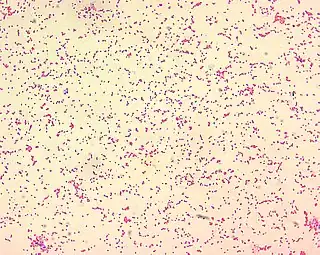

El género Brucella está constituido por bacilos gram negativos pequeños, sin movilidad, aerobios estrictos, sin cápsula y no forman esporas. Se describen seis especies clásicas, las cuales se han diferenciado con base en sus características antigénicas y su hospedador animal preferencial: B. melitensis (oveja, cabra, camello); B. abortus (ternera, búfalo, camello, yak); B. suis (cerdo, liebre, reno, roedor, caribú); B. canis (perro); B. neotomae (roedores) y B. ovis (ovejas).[5][10]